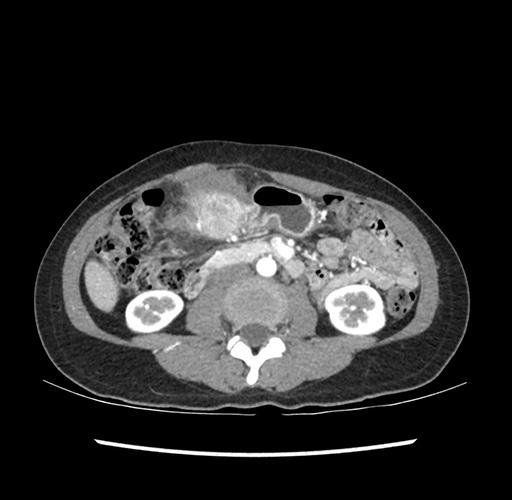

Imaging Analysis

Look through the patient's CT scan to identify any areas of concern for the necessary procedure.

Based on your CT findings, which issue(s) would give reason for "planned slowing down moment(s)" in this case?